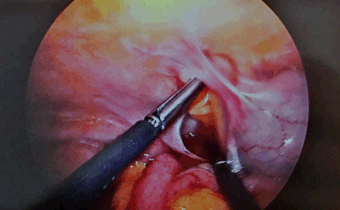

The patient was taken to theatre for laparoscopy within 24 hours of admission. A paracecal hernia containing an obstructing loop of jejunum was identified between the cecum and lateral abdominal wall. Multiple adhesions in this area created a narrow necked blind ending ‘hernia cave’ in the right paracolic gutter. An adjacent internal hernia contained an unobstructed vermiform appendix. Laparoscopic reduction of the small bowel from the hernia was performed and adhesiolysis undertaken to prevent recurrence. The patient had an uncomplicated postoperative course, returned to baseline function and was discharged on the third postoperative day.

Figure 3: (A, B) Intraoperative images of the paracecal hernia caused by multiple adhesions.

Figure 4: Laparoscopic reduction of the hernia.